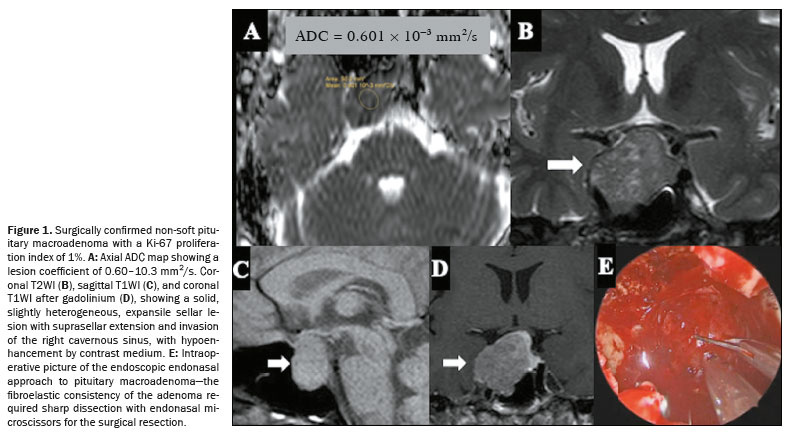

On DWI, a less frequently observed pattern of pituitary macroadenomas is one of lesions showing ADC values of 0.5–1.0 × 10−3 mm2/s. That ADC range has been linked to a higher probability that a tumor will have a non-soft consistency, as illustrated in the probability contour maps generated by the machine learning model. This imaging phenotype may indicate increased tissue cellularity or reduced extracellular space, features commonly associated with fibrous adenomas. However, the relationship between the ADC and tumor consistency appears to be nonlinear and may be influenced by other factors, such as tumor diameter, patient age, and patient sex. The heterogeneous nature of pituitary macroadenomas, including the coexistence of fibrotic and nonfibrotic areas (Figure 1), may account for the variability in ADC behavior, supporting the idea that ADC alone is inadequate to predict consistency with high reliability(21).

The consistency of a tumor, whether soft or non-soft, significantly influences surgical planning and requires skilled handling of various surgical tools. Soft tumors can often be removed easily using methods like aspiration or blunt curettage. However, approximately 10–15% of tumors are non-soft, posing significant technical challenges, with lower rates of complete resection and a higher risk of postoperative pituitary dysfunction

(22). In these situations, sharp instruments, curettage, ultrasonic aspirators, increased surgical access, or even craniotomy may be necessary